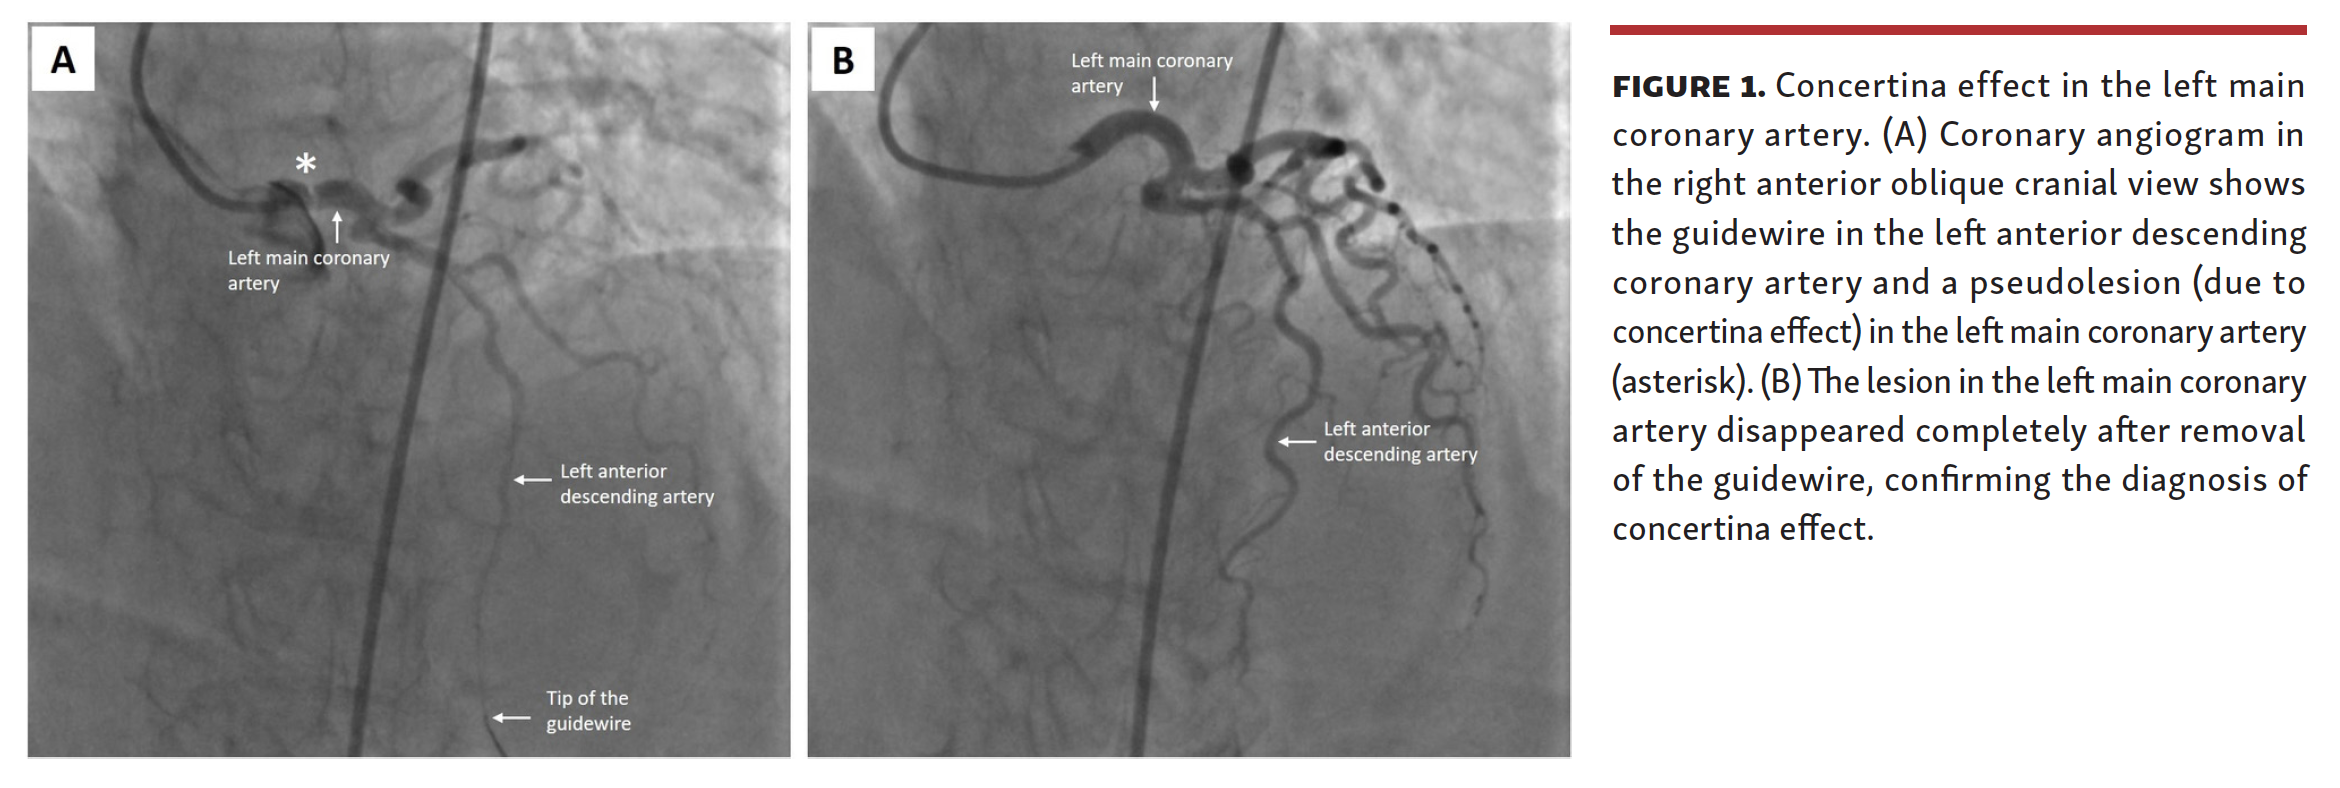

A Phantom Lesion in the Left Main Coronary Artery Concertina Effect Definition Of Concertina Effect the concertina effect is the progressive shortening of pr interval with corresponding widening of the qrs complex. 1 it occurs due to straightening of a tortuous coronary artery by a coronary equipment that stretches the artery, which leads to invagination of excess tissue. the concertina effect is the progressive shortening of pr interval with. accordion effect or. Definition Of Concertina Effect.

Concertina Effect Definition Of Concertina Effect the concertina effect is the progressive shortening of pr interval with. accordion effect or concertina effect — also known as “crumpled coronary” — is an uncommon occurrence during coronary. concertina effect or accordion effect is angiographic appearance of a tortuous coronary vessel after being crossed with a guidewire. concertina effect or accordion effect is angiographic appearance. Definition Of Concertina Effect.